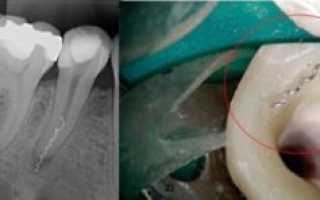

После пломбирования каналов материал оказался за пределами корня

- ошибки в пломбировании канала (неплотное заполнение канала композитом, выход цемента за контур зуба, перфорация канала или корня, инородное тело в полости зуба и т.д.),

Помимо перфорации стоматолог может допустить и другие ошибки. Частой ошибкой является выведение пломбировочного материала за изначальную форму зуба. Подобное особенно неприятно при глубоком пломбировании каналов корней зуба. Может возникнуть боль при накусывании, образоваться отечность и гиперемия.

Перфорация зубных корней

Другими словами – прокол корня, проделывание в нем отверстия. Это может привести к попаданию пломбировочного материала в периодонт (ткань между корнем зуба и костью). Очень тяжелые случаи, при которых боли длятся до полугода.